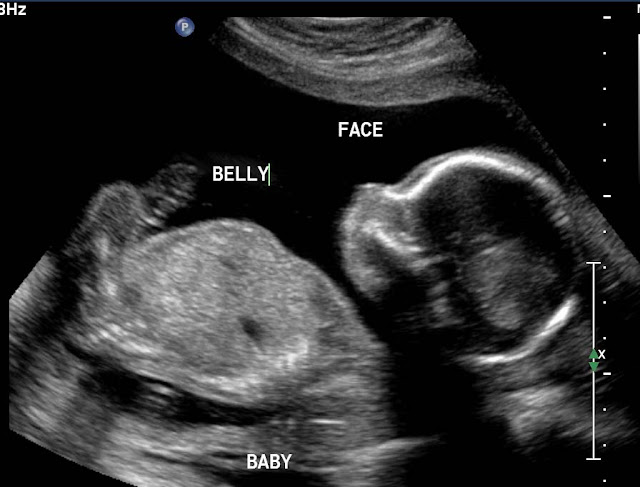

It's a...

BABY!

And a pretty cute one at that.

If I do say so myself.